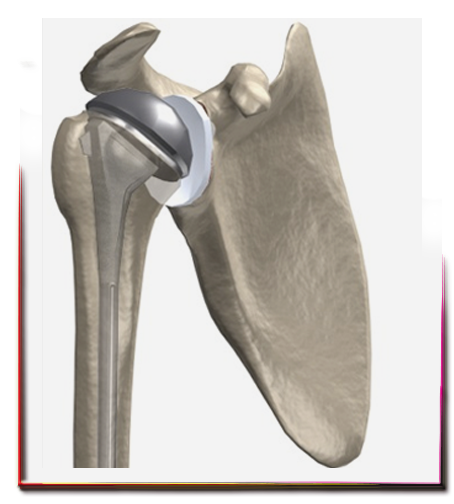

Omuz kırığında protez ameliyatı ne zaman gerekir?

Bazen yaralanma, kırık parçalarına, tespiti mümkün olamayacak kadar fazla zarar verir. Çok parçalı kırıklı çıkıklar, parçaların tespit edilemeyecek kadar ince ve osteoprotik olduğu durumlarda hastanın yaşam kalitesinin arttırılması ve ağrısının sona erdirilmesi amacıyla protez cerrahisi kullanılabilir.